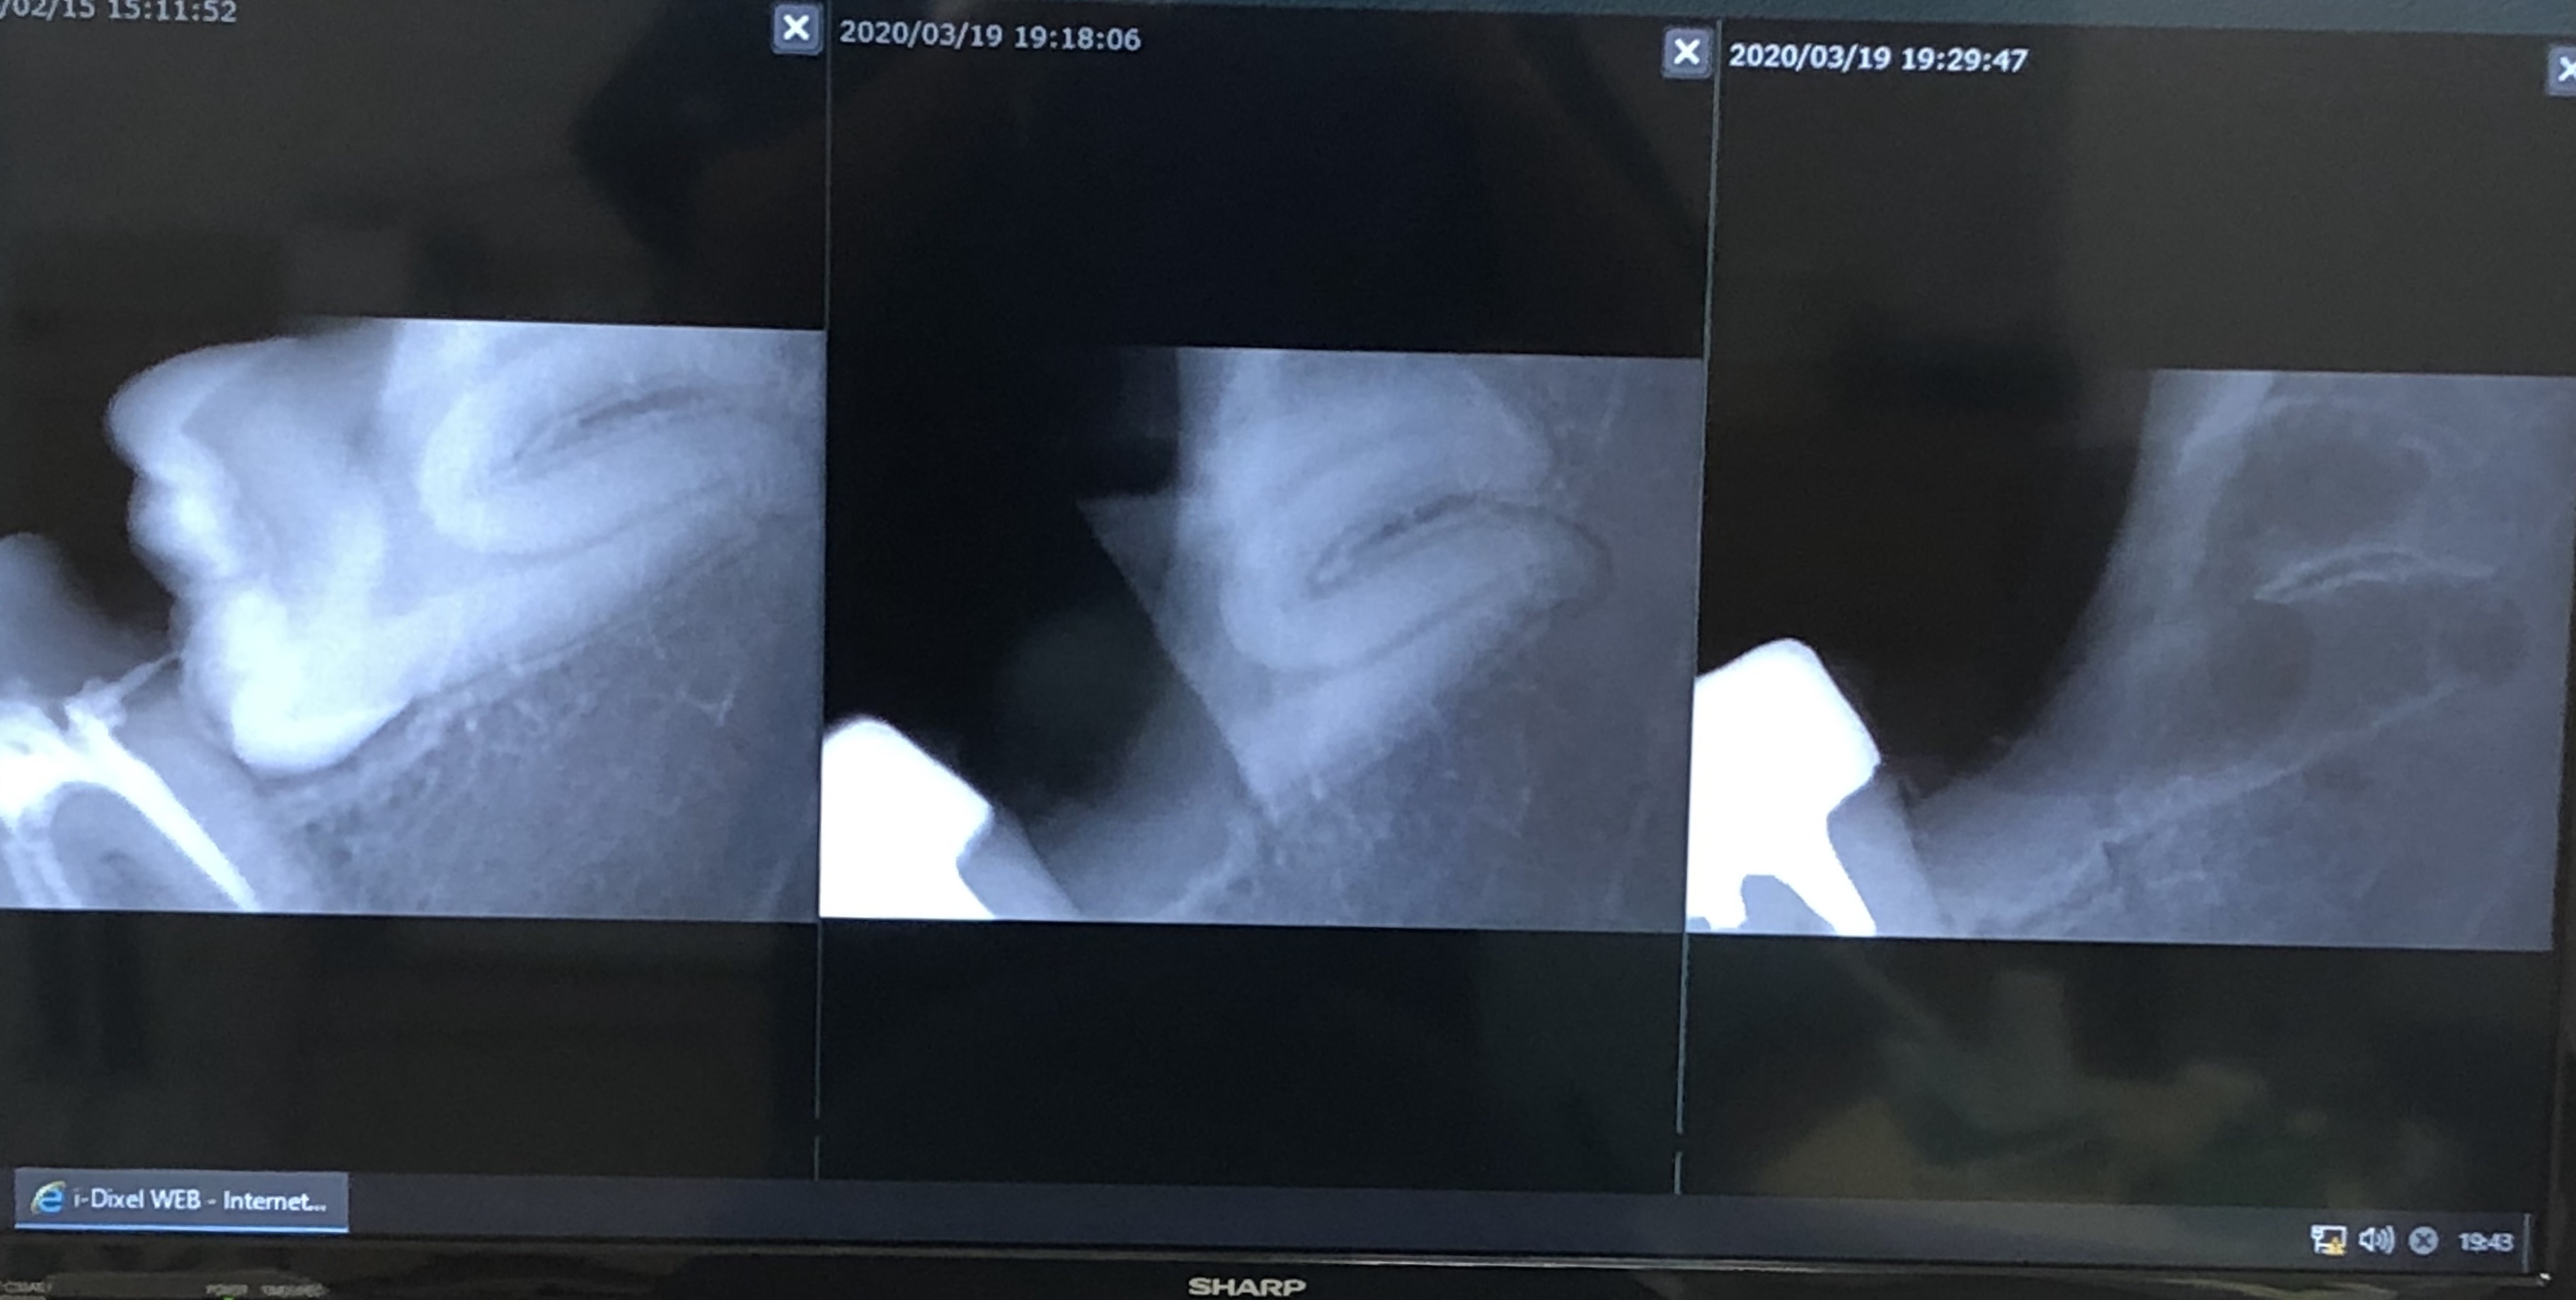

おやしらず

こんにちは院長の酒井です。 昨日、親知らずの抜歯を行いました。 横向きに生えていて、歯が大きか...

親知らず

こんにちは院長の酒井です。 今日は診療終了後にスタッフの親知らずを抜歯しました。 今回は完全に...